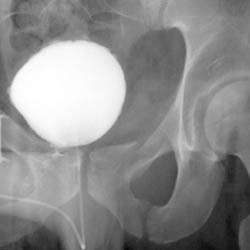

Skeletal Trauma > Pelvis & Hips > Pelvis and Hips Quiz

Pelvis and Hips Quiz

True or False 1. Posterior hip dislocations are less common than anterior. 2. Malgaigne fractures are unstable. | ||||||